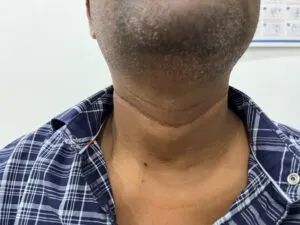

Well placed neck scar for thyroidectomy heals well and align with neck folds so that it is not visible obviously after 4 months of surgery. Steps taken to produce a fine thyroidectomy scar

1) Incision placed in natural neck fold.

2) Sub-cutaneous suturing done with absorbable sutures so that scar is thin.

This patient underwent thyroidectomy with neck dissection on both side of neck with 10 cm incision which is well healed .

Another fine thyroidectomy with neck dissection scar for cancer of thyroid.